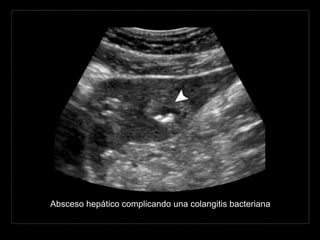

Complicaciones

Agudas

• abscesos hepáticos

• trombosis de la vena

porta

• peritonitis biliar

Crónicas

• estenosis biliar

• colangitis esclerosante

• colangiocarcinoma

Absceso hepático complicando una colangitis bacteriana